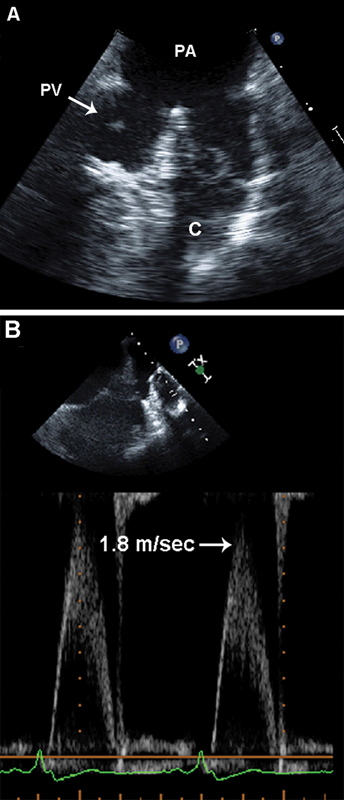

فحوصات تشخيصية لبعض امراض القلب والشرايين التاجية